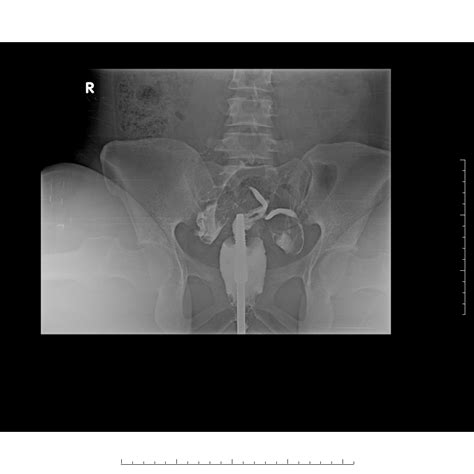

When individuals search for Didelphic Uterus Pictures, they are often seeking clarity on how their anatomy differs from the standard uterine structure. Medical imagery, such as MRIs, ultrasounds, and 3D pelvic reconstructions, provides the best visual representation of this double structure. Unlike a bicornuate uterus—where the two horns are connected—the Didelphic uterus consists of two completely independent units.

Viewing these medical images helps patients understand why they may experience certain symptoms. For example, the presence of two cervices is a hallmark feature visible in clinical scans. Understanding these visuals can help patients communicate more effectively with their gynecologists during consultations.

| Hysterosalpingography | Used to observe the shape of the uterine cavities using dye. |